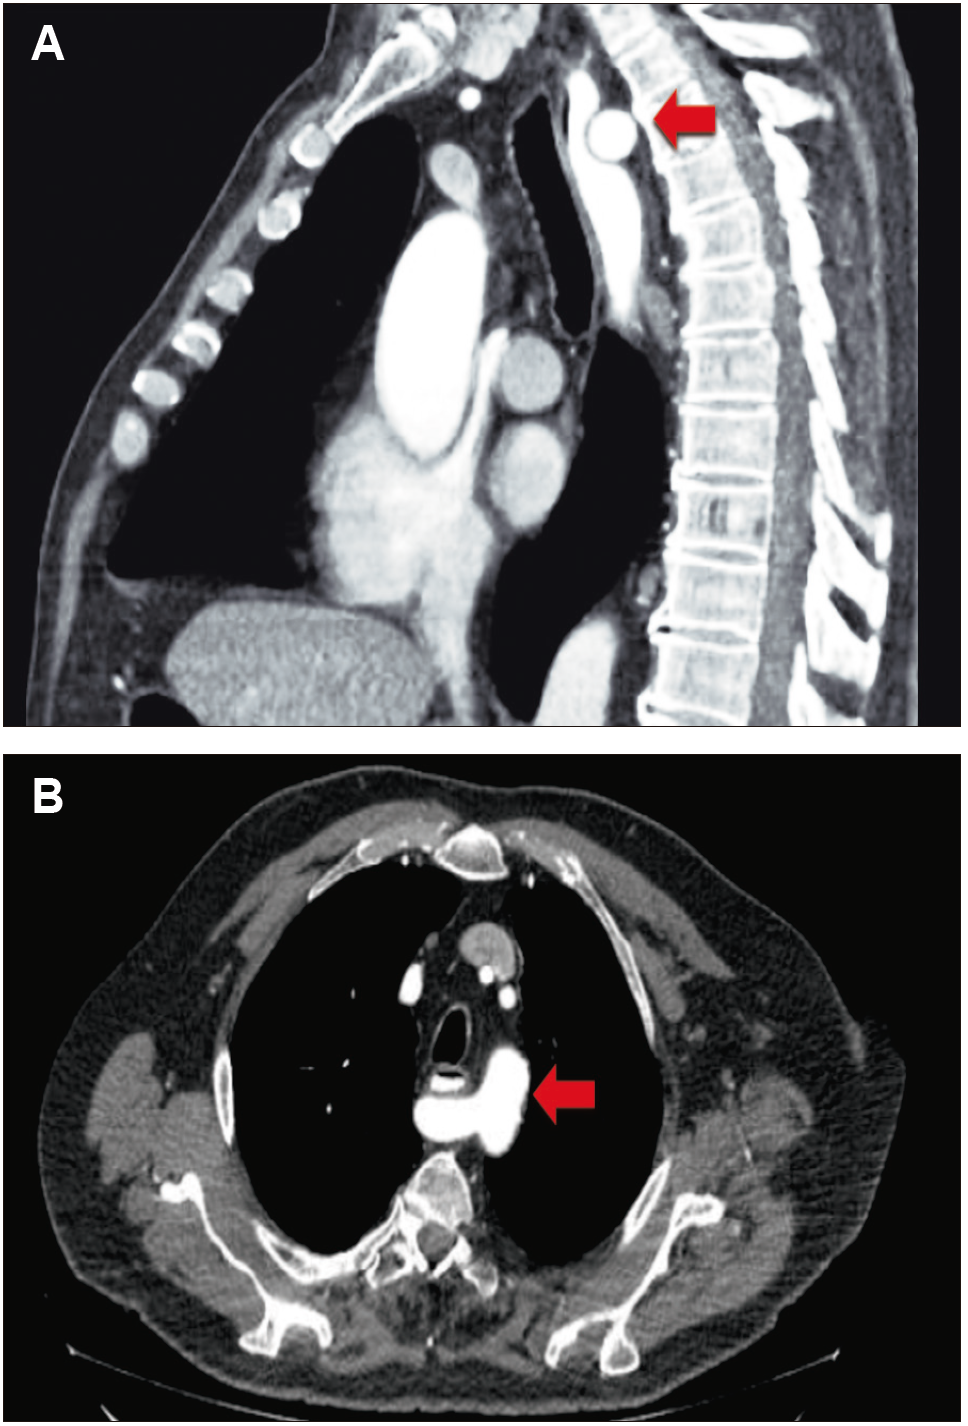

Varón de 79 años de edad, con antecedentes de diabetes tipo 2 e hipertensión arterial que fue derivado al sector de Neurogastroenterología con diagnóstico de disfagia lusoria. Refería disfagia esofágica intermitente a sólidos y líquidos de 4 meses de evolución asociada a dolor torácico irradiado al dorso y regurgitación, sin mejoría con IBP. El examen físico fue normal. Concurrió a la consulta con una VEDA donde se constató una dilatación de la luz esofágica y una pequeña hernia hiatal por deslizamiento, y con una angio-TC de tórax donde se informó una arteria subclavia derecha aberrante con compresión de la cara posterior del esófago y dilatación del mismo (Figura 1).

Figura 1. A. En el corte sagital de la angiografía por TC tórax se

observa una arteria subclavia derecha (flecha) que comprime e impronta la cara posterior del esófago. B.

En el corte axial de la Angio-TC se evidencia la arteria subclavia derecha aberrante (flecha) que

impronta y comprime la cara posterior del esófago